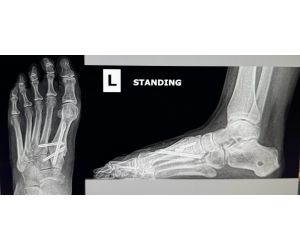

Syndesmotic Injury - What Would You Do?

Spencer Keane, DPM

46 yo F walks into clinic. Previously diagnosed with b/l ankle arthritis and has been wearing lace up ankle braces for over a year. Left ankle is...